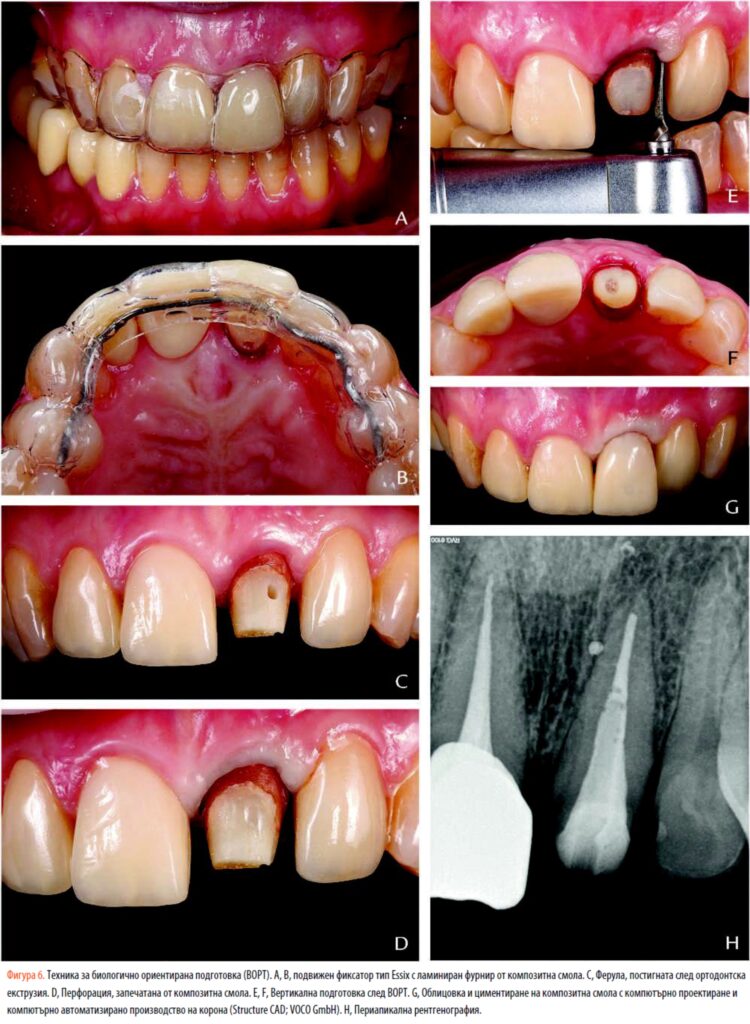

Впоследствие цервикалната област на сърцевината беше перфорирана напречно с високоскоростен диамантен въртящ се инструмент (859-010; Intensiv AS), като се внимава да не се повреди влакнестият стълб (фиг. 4). Интракороналните еластични и метални лигатури бяха поставени през създадения отвор и бяха сменяни всяка седмица в продължение на 3 седмици.(24) Метален щифт с дебелина 1,5 mm беше адаптиран към палатиналните повърхности на предните зъби за закрепване на ортодонтската тракция и беше циментиран в максиларните кучешки зъби и първи премолари с композитна смола за насипно пълнене (SDR Flow; Dentsply Sirona) (фиг. 5).

На всеки седмичен ангажимент по време на активния период на екструзия е извършена периферна супракрестална фиберотомия, за да се предотврати коронарното изместване на гингивалния ръб. Подвижен фиксатор тип Essix с композитен ламиниран фурнир от смола беше произведен като междинно възстановяване (фиг. 6A, 6B). По време на фазата на екструзия периодично се правят периапикални рентгенографии, за да се определи степента на коронарното изместване и състоянието на периодонталния лигамент. Процедурата приключи, когато повърхността на корена беше достатъчно разкрита, за да се осигури оптимална ферула за протезата.

Тази ортодонтска техника осигурява 2,0 mm екструзия, постигайки втулка от около 3,0 mm букално и палатално и 2,5 mm интерпроксимално (фиг. 6C, 6D). След 6 седмици на задържане, зъбът беше вертикално подготвен чрез следване на техниката BOPT (фиг. 6EH). 25 Компютърно проектирана и компютърно произведена (CAD-CAM) коронка от композитна смола (Structur CAD; VOCO GmbH) беше пренастроен и адаптиран за моделиране на меките тъкани и беше поставен с междинен цимент за 3 месеца, за да се постигне гингивален контур, подобен на този на съседния зъб (фиг. 6G). Окончателното възстановяване от цирконий (Zirlux), наслоено с фелдшпатов порцелан, беше циментирано със самозалепващ се универсален цимент от смола (Calibra Universal bleach; Dentsply Sirona) (фиг. 7). 0,5 mm лента от полиран цирконий беше оставена в контакт с профила на поява.